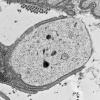

PERIPHERAL NEUROPATHY

7B CIDP (8)